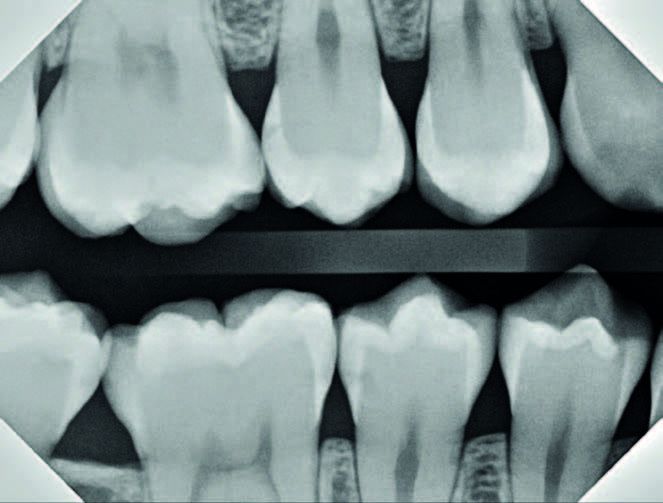

If you are anything like me, you would have recommended some watches, and some class II fillings. That’s what I did for over 20 years. And I now really regret it. Sadly, for a variety of reasons, neither is a great option. First, drilling is barbaric, destructive, and incredibly invasive. Let’s zoom in on the anterior right radiograph [Figure 2].

More than likely, the majority of you believe that #4, #29, #30 and #31 require some kind of intervention. At the very least, they shouldn’t be completely ignored. If you received your dental training similar to mine (I graduated from the University of Michigan in 2004), then it is within the realm of possibility that you would recommend quite a few MOs and DOs, maybe even an MOD for #30.

In order to adequately remove all the decay for all of these restorations, you would have to, access the interproximal surface via an occlusal prep; break all interproximal contact in order to place a band; bevel cavosurface enamel; round any sharp angles between the walls in the proximal box.

All of those steps involve destruction of healthy enamel and dentin. Your prep would end up looking something like [Figure 3]. Relative to the size of the cavity, that is a lot of enamel destruction.